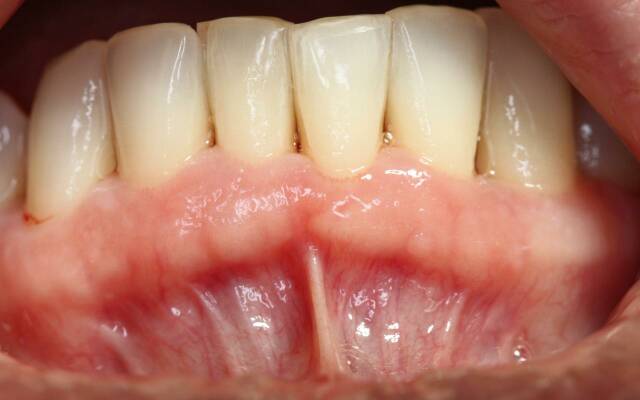

Найважливішою ознакою пародонтозу є поступово прогресуюча деградація тканин, що оточують зуб. Атрофія і остеопороз кісткової тканини альвеоли проявляється оголенням шийок і навіть коріння зубів. Десни в зоні ураження часто мають бліде забарвлення. Нерідко відзначається підвищена кровоточивість ясен, особливо — при відкушуванні досить твердої їжі. Зубні відкладення (м'які або мінералізовані), як правило, незначні. Пацієнт може також скаржитися на відчуття свербіння в яснах і неприємний запах з рота. Часто спостерігається підвищена стертість емалі зубів.

На початкових стадіях розвитку хвороби зуб добре зафіксований, але в міру прогресування починає розвиватися патологічна рухливість внаслідок дегенеративного ураження утримують його зв'язок і резорбції кісткової тканини альвеоли.

Пародонтоз можна з високою часткою ймовірності припускати, якщо в ході огляду виявляються витончення і «усадка» ясенного краю з оголенням шийок зубів. Важливою ознакою також є виявлення в процесі зондування надто глибокого патологічного «кишені» між коренем і м'якими тканинами.